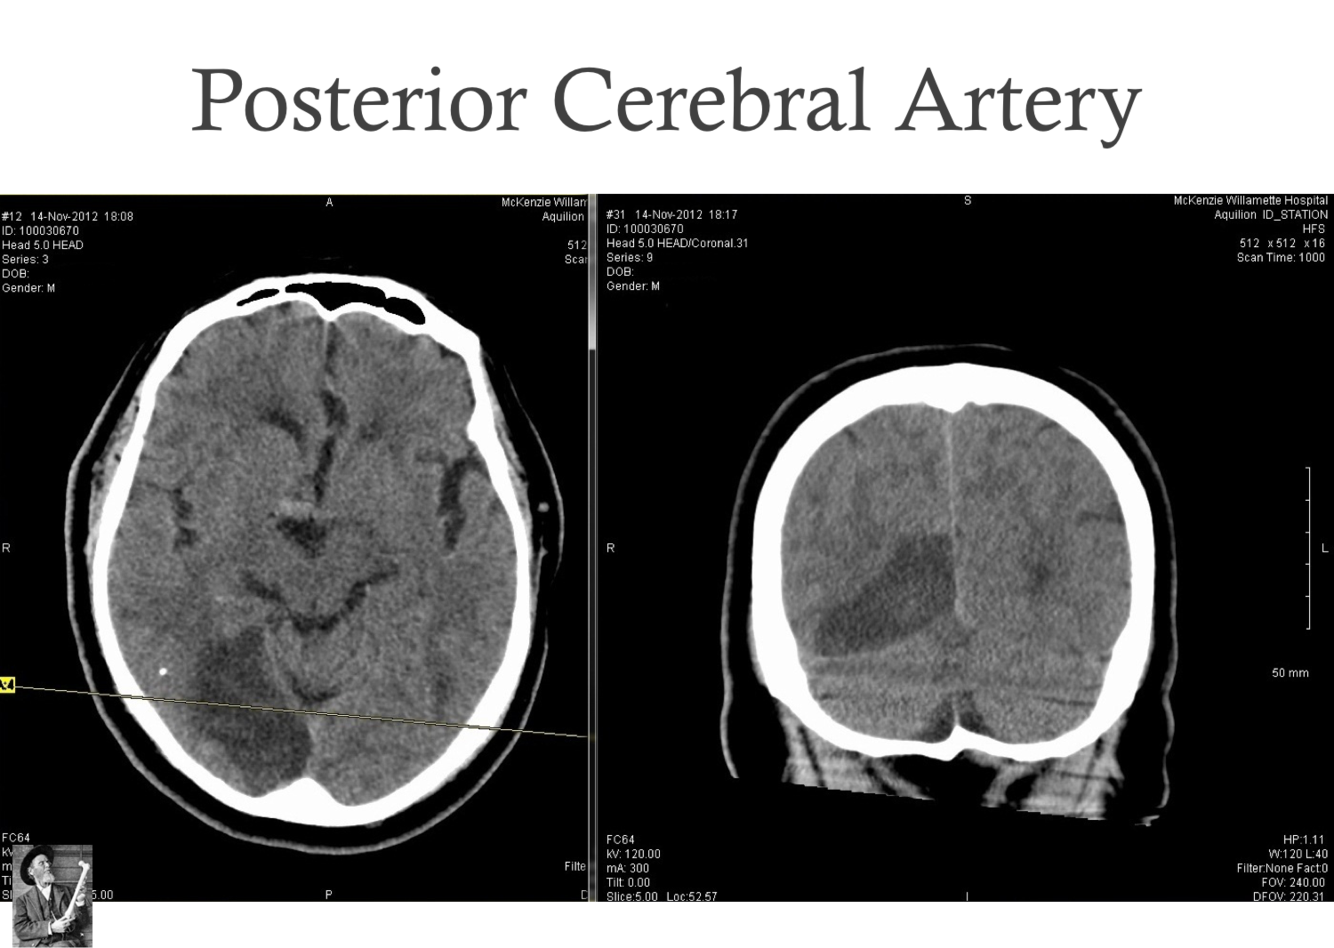

What symptoms would you find in a ischemic posterior cerebral artery?

affects mostly the occipital lobe and will have mostly visual field defects?